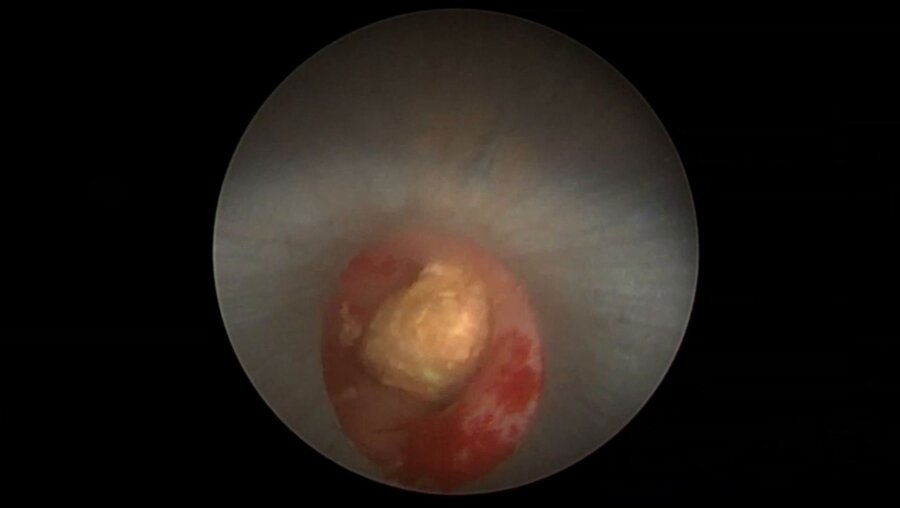

II – Урологическая школа тулиевых технологий

11

Россия, Москва

27 фев 2019

1490 просмотров